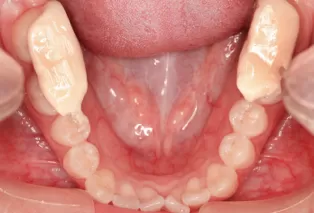

Intraoral photos